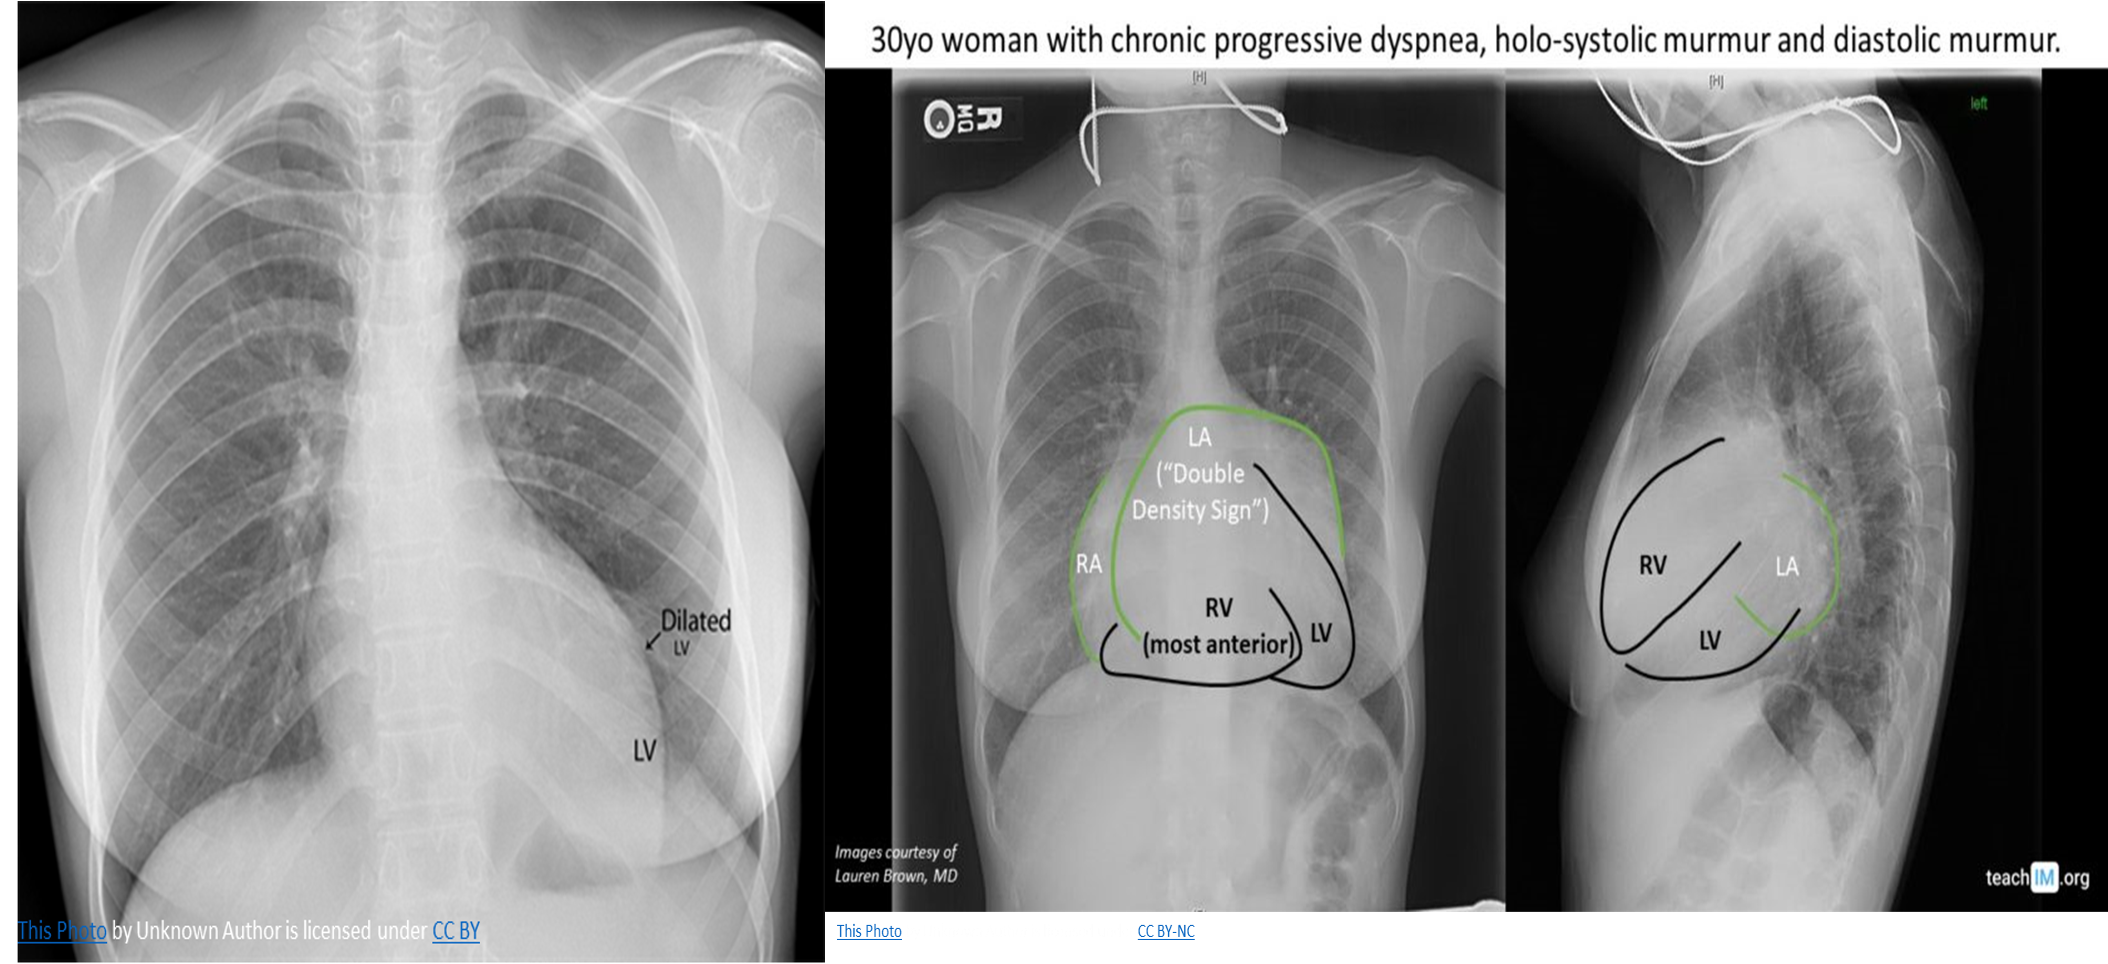

CXR

• Cardiomegaly: enlarged left atrium and ventricle

• Signs of congestive heart failure

• Acute MR: heart size is usually normal but shows pulmonary edema (alveolar edema).